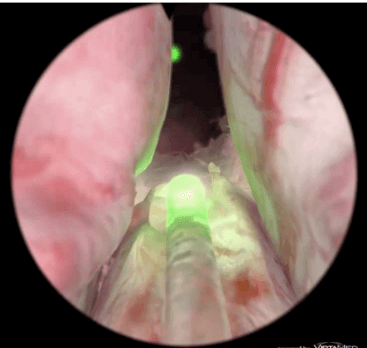

Tam böylesi sorunların zihinleri meşgul ettiği günlerde klinik kullanıma Yeşil Işık (GreenLight) Lazer Ameliyatı geldi (Resim 2). Bu teknik; prostat dokusunu çıkarmadan, olduğu yerde, lazer enerjisinin ısı etkisiyle buharlaştırarak ortadan kaldırıyordu. Göreceli kısa ameliyat süresi, yan etki sıklığının azlığı, cinsel yaşama ilişkin yan etki oranının düşük olması yüksek maliyetine rağmen cazibe kazanmasını sağladı.

Resim 2: Yeşil Işık Lazer Tekniği ile prostat ameliyatı.